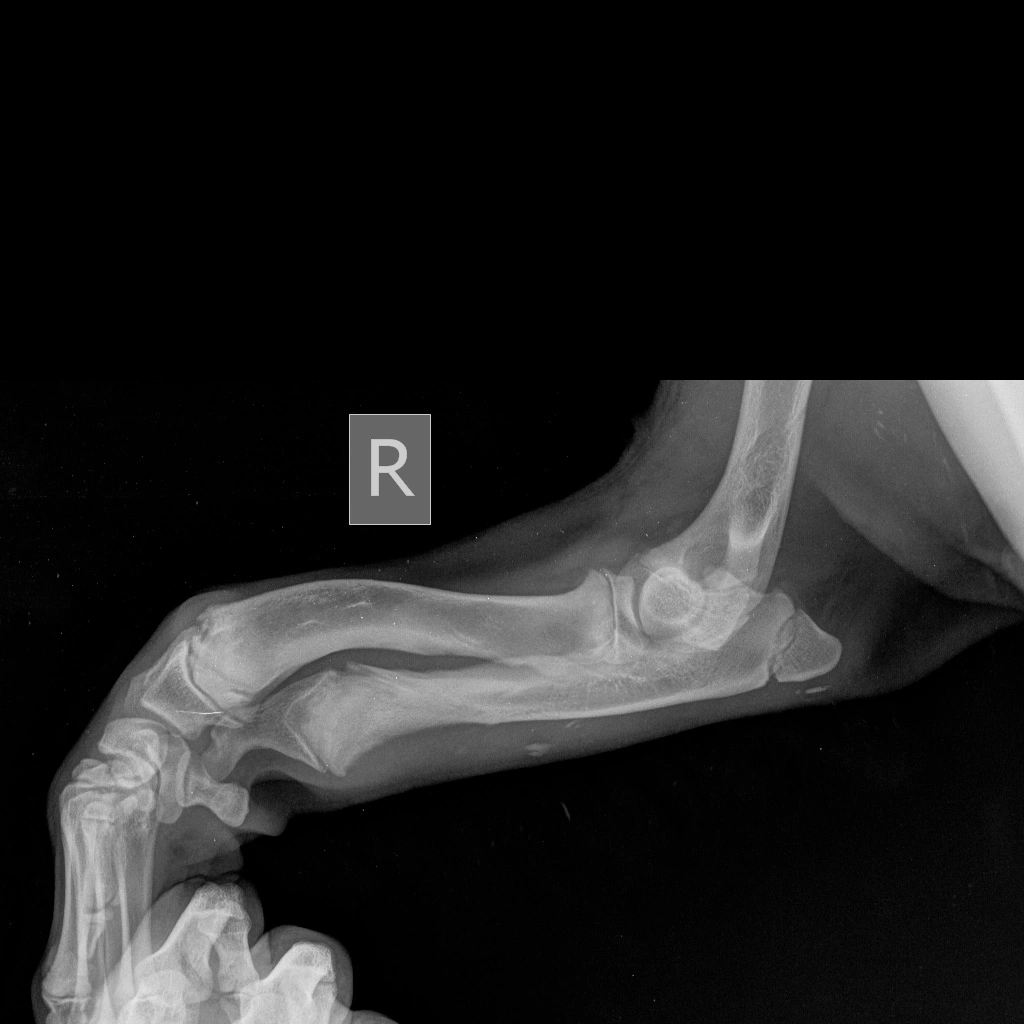

Предплечье состоит из двух костей (лучевой и локтевой), в норме они развиваются синхронно. При заболевании отмечается раннее закрытие зоны роста локтевой кости, что останавливает ее рост, в то время как лучевая кость продолжает увеличиваться в длину. Дальнейшему росту кости препятствуют локтевые и запястные суставы, что вызывает избыточное давление на них и искривление самой кости. Патологическое давление на сустав вызывает развитие дегенеративного изменения хряща (артроза, артрита, остеоартрита).

Основными клиническим признаками является нарастающая хромота и искривление лап в области запястья (так называемый «размет лап», а также припухлость в области локтевого сустава и его малоподвижность).

Диагноз ставится на основании анамнеза, ортопедического осмотра и инструментальных методов диагностики, таких как рентгенография и компьютерная томография (КТ), при которых врач может оценить стадию заболевания и выбрать подходящую тактику лечения.